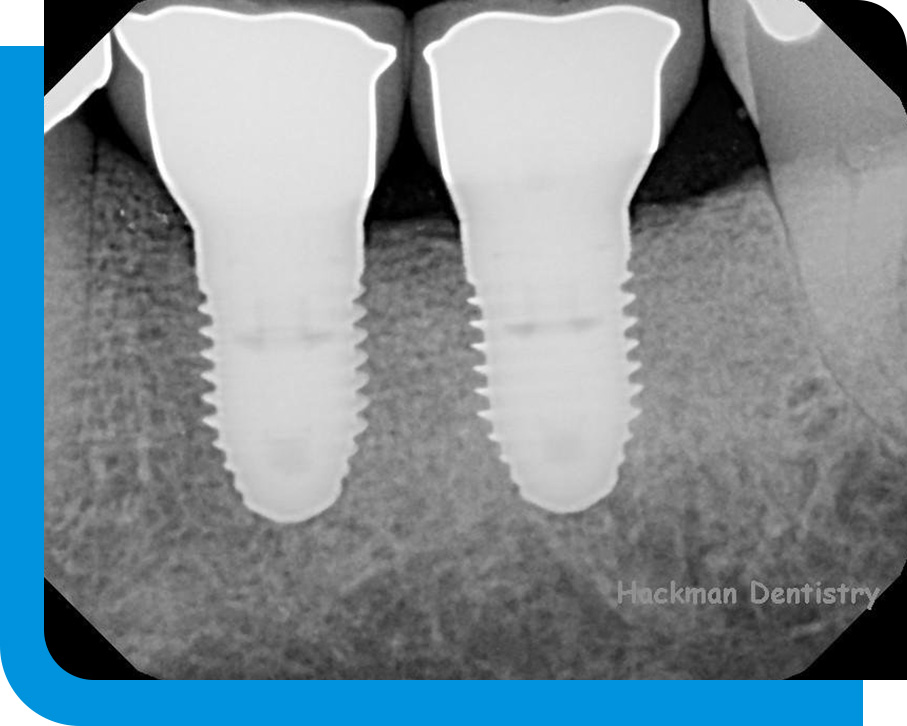

Over the course of a few months, the full implant procedure is carried out. Installing the implant itself, which involves driving a screw into the jaw bone, is the first step in the procedure. In order to put the implant, a gum incision must be made. If necessary, multiple implants may be inserted simultaneously. The gums are stitched once the implants have been inserted.

The osseointegration process, which takes between 3-6 months to complete, causes the jaw bone to surround the implant as it heals.

Dental implants are simply titanium cylinders that are anchored firmly in the jawbone. The replacement teeth are supported by the implants. They are successful and enduring.